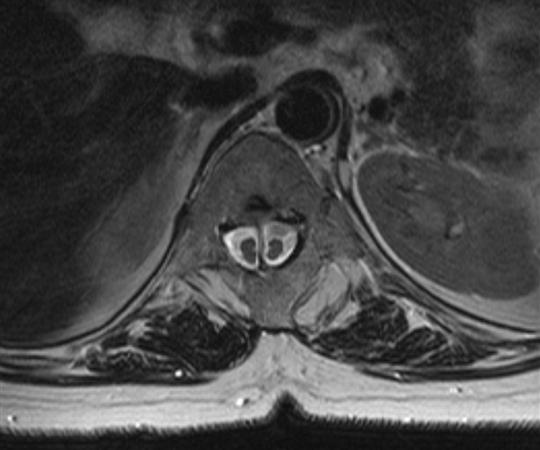

Migrasyon Gösteren Disk Protrüzyonu, Sekestre Disk Hernisi, Faset Kisti Nedir ve Hareket Koruyucu Cerrahi, Hareketli Platin Ameliyatı, Protez Ameliyatı Nasıl Yapılır?

Halk arasında patlamış fıtık veya kanala düşmüş fıtık ta denen disk protrüzyonu veya başka bir deyimle sekestre disk hernisi durumuna ...